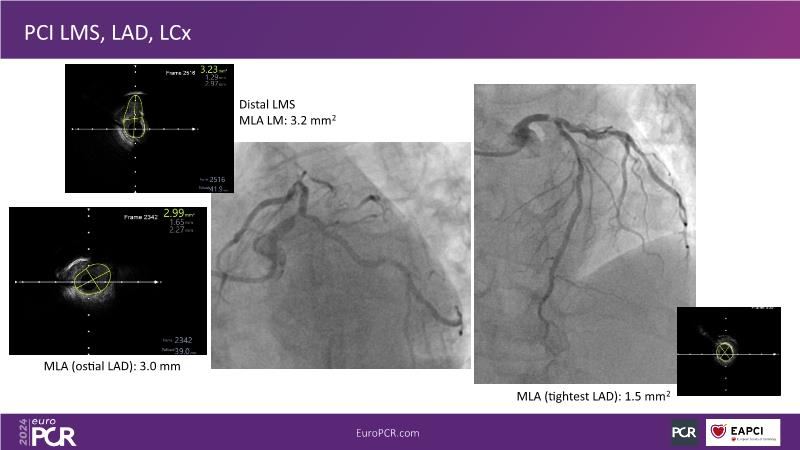

From innovation to reality: the impact of Cre8 EVO technology on complex PCI

This session is a good opportunity to delve into the contemporary technical and clinical complexities surrounding complex PCIs in challenging patient cases. Explore the necessary tools and treatment strategies to enhance peri-procedural and long-term clinical outcomes, and follow discussions on the unique technologies of Cre8 EVO in complex PCI scenarios.